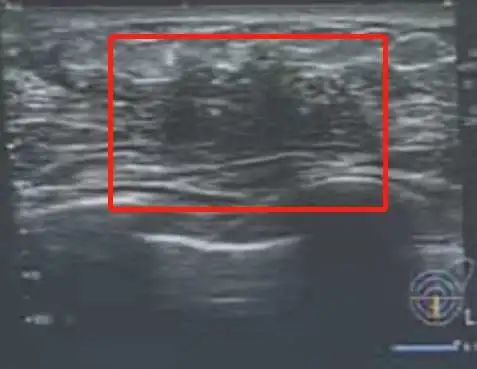

乳腺彩超

图片来源:肖伟锴医生提供也就是乳腺超声,超声检查的原理是利用不同组织的对声音的阻挡能力不同,最终反射回来的声波不同,从而区分乳腺内是否异常病灶。

乳腺彩超的优势就是显示结节更清楚,但是对小钙化灶的显示能力有限。乳腺彩超的优点就是无辐射,非常安全,简单快捷,当场可以拿报告,价格也相对便宜。

孕期和哺乳期的也可以乳腺彩超检查。对于小于 40 岁的年轻女性更适合做乳腺彩超检查。